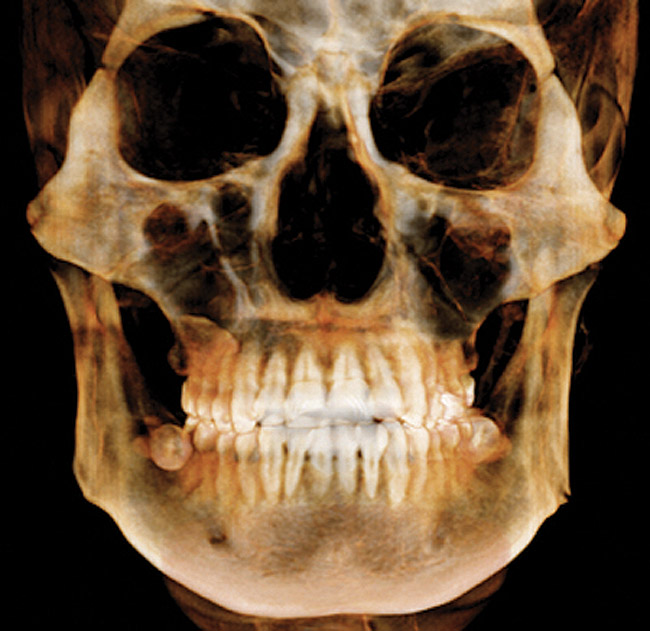

(3.) CBCT scan showing 3-dimensional rendering of both arches.

Figure 3

CBCT

CBCT is indicated for the following: implant planning; developing surgical guides; general observation; finding the correct number of canals in abscessed teeth requiring endodontic treatment; in some cases, for orthodontic planning for patients with asymmetries or who need surgical procedures; for evaluation of impacted teeth or TMJ; and as an adjunct for intraoral imaging. Perhaps the most important CBCT advantage is that it offers a “third dimension” for diagnostic accuracy (Figure 3).22

Other benefits include: its short scan time; nearly immediate availability of images; compatibility with practice management software; ability to identify a variety of incidental findings, such as carotid artery calcifications; and facilitate patient communication/education. Like any imaging in dentistry, CBCT should only be used for dental purposes, but incidental findings should be recorded when they are present. CBCT should not be used specifically for screening for carotid calcification, as Duplex Doppler ultrasound is the method of choice for inspecting blood clots in the carotids. When calcification is found in the carotids, or other conditions of general health importance are found, the patient should be referred to the appropriate physician for further follow-up and treatment if needed. While there is a learning curve for reading the full image volumes, there are services available for this. Like CBCT, it is extraoral, so its advantages include that it is more comfortable for patients and can be used in patients who cannot tolerate having a sensor or film in their mouths. It can also be used when intraoral scanning is not practical—eg, for a panoramic bitewing.